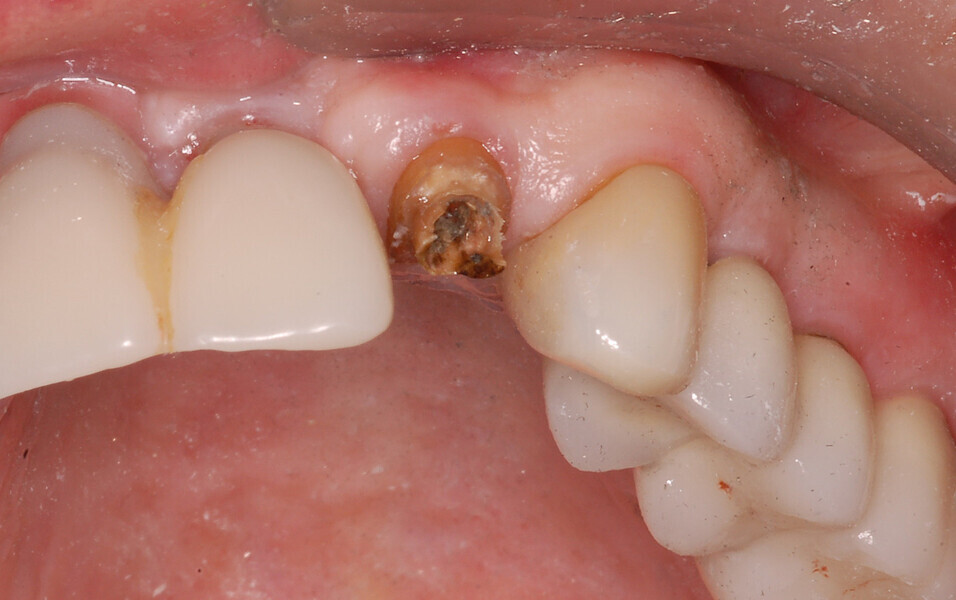

Fig. 18: A periapical radiograph

with a drill in place confirmed that the apex length had been reached and that all the gutta-percha had been removed.